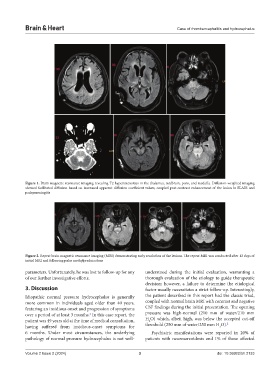

Figure 1. Brain magnetic resonance imaging revealing T2 hyperintensities in the thalamus, midbrain, pons, and medulla. Diffusion-weighted imaging

showed facilitated diffusion based on increased apparent diffusion coefficient values, coupled post-contrast enhancement of the lesion in FLAIR and

pachymeningitis

Figure 2. Repeat brain magnetic resonance imaging (MRI) demonstrating early resolution of the lesions. The repeat MRI was conducted after 12 days of

initial MRI and following pulse methylprednisolone